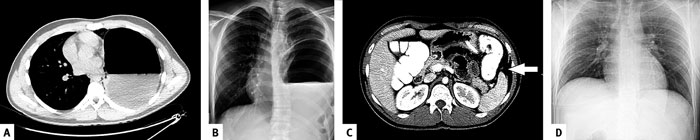

DT är troligtvis den mest användbara diagnostiska metoden vid trauma i dag [9]. En nackdel är att den tar ungefär 20–30 minuter att genomföra, varför patienten behöver vara hemodynamiskt stabil. I vår studie var sensitiviteten för att upptäcka traumatisk diafragmaruptur med DT 66 procent, vilket kan jämföras med tidigare studier, som rapporterat 60–80 procent [4-7, 12]. Skillnaden i sensitivitet vid trubbigt och penetrerande trauma var i vårt material mycket stor (93 respektive 36 procent). Det kan förklaras av att rupturen vid penetrerande trauma är mindre och att herniering därmed också är sällsynt (Figur 1). Eftergranskning eller upprepad DT-undersökning kan i vissa fall av misstänkt traumatisk diafragmaruptur vara av värde, särskilt vid penetrerande trauma. I vår studie kunde två fall med traumatisk diafragmaruptur efter penetrerande trauma fastställas på detta sätt. Vid stark klinisk misstanke om traumatisk diafragmaruptur vid penetrerande trauma bör kompletterande laparotomi eller laparoskopi övervägas, även när DT är negativ.

Figur 1. DT- och lungröntgenbilder vid traumatisk diafragmaruptur efter trubbigt (A och B) respektive penetrerande trauma (C och D). A: DT-bild med normal lungvävnad på höger sida och hernierad ventrikel på vänster sida. B: Frontal lungröntgenbild som visar herniering av ventrikel med tydlig vätskenivå i ventrikeln på vänster sida. C: DT-bild som visar en misstänkt ca 2,5 cm stor rift dorsalt i diafragma med fett som buktar in i pleura (pil). D: Frontal lungröntgen, på samma patient som i bild C, som var normal.